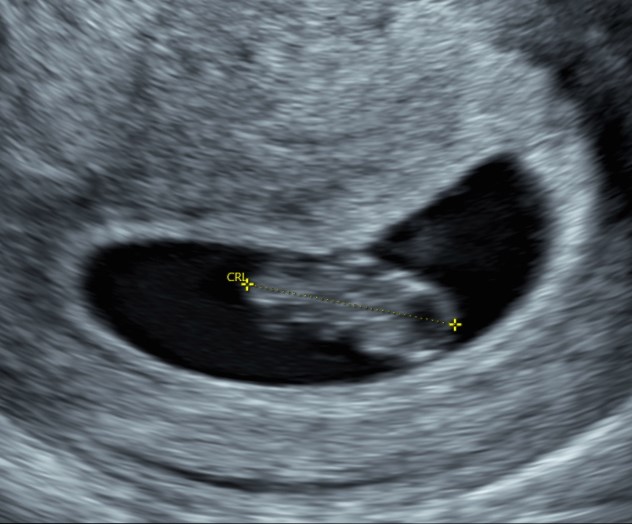

Il vostro ginecologo dopo aver visto il battito misurerà il “tesorino”, dalla testa alla coda con una misurazione che si chiama CRL (Crown Rump Length – Distanza testa coda).

Di seguito una piccola tabella dove son riportate le corrispondenze:

| Settimane di Gravidanza | CRL (mm) | Peso (g) |

| 6 settimane | 4 mm | |

| 7 settimane | 11 mm | < 1g |

| 8 settimane | 17 mm | 1 g |

| 9 settimane | 23 mm | 2 g |

| 10 settimane | 34 mm | 4 g |

| 11 settimane | 44 mm | 7 g |

| 12 settimane | 57 mm | 14 g |

| 13 settimane | 68 mm | 23 g |

| 14 settimane | 81 mm | 43 g |

Misurando il tesoro è possibile quindi sapere la corretta epoca gestazionale nella quale ci troviamo.